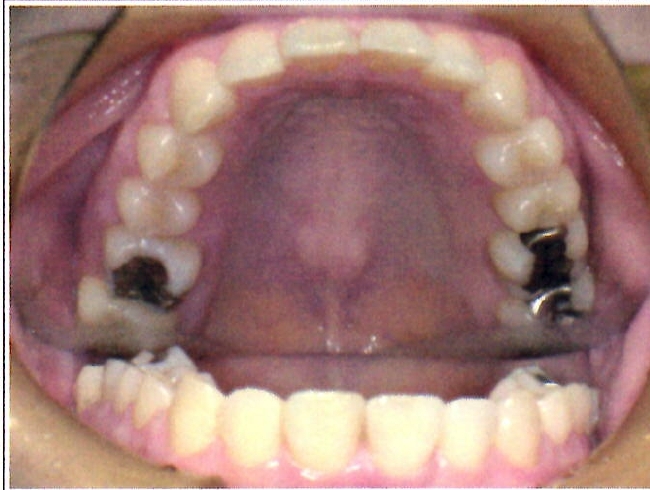

| 主訴・治療前の状態 | 下顎前歯部に叢生(ガタガタ)があり、歯ブラシが届きにくく清掃性に問題がありました。また、見た目も気にされていました。 |

| 治療内容 | 下顎前歯を1本のみ抜歯し、歯列を整えました。治療に際しては、ブラックトライアングル(歯と歯の間の歯茎部分に三角形の隙間ができること)が生じる可能性について事前に説明し、患者様にご了承いただいた上で治療を開始しました。 |

| 治療結果 | 予定通りの仕上がりとなり、事前説明の通りブラックトライアングルは生じましたが、患者様には十分ご理解いただいており、満足度の高い結果となりました。 |